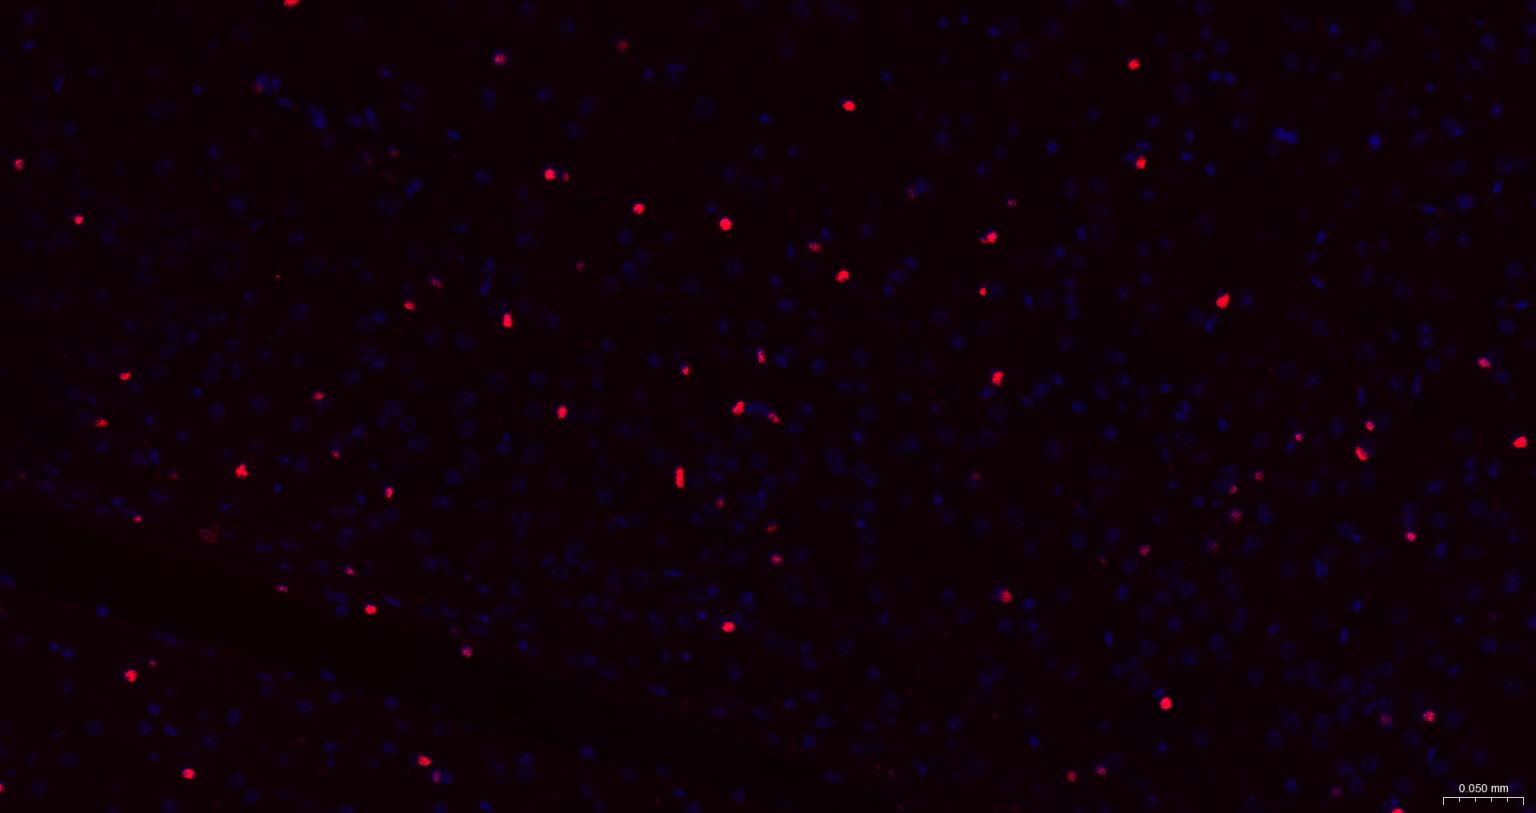

Paraformaldehyde-fixed, paraffin embedded Mouse Cerebrum; Antigen retrieval by boiling in sodium citrate buffer (pH6.0) for 15 min; The section was incubated with SOX10 Monoclonal Antibody, Unconjugated (bsm-60234R) at 1:200 overnight at 4°C. Followed by conjugated Goat Anti-Rabbit IgG antibody (Red, bs-0295G-BF594), DAPI (blue, C02-04002) was used to stain the cell nuclei.